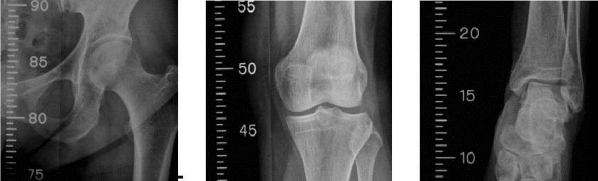

Radiological evaluation is generally not needed when evaluating patients with pigeon toes. The "foot progression angle" (FPA) must be taken into account: this is the angle formed by the length of the foot and the line of the walking path ("straight ahead" when the patient walks). A negative FPA indicates the inner bushing, a positive FPA indicates the outer bushing. The amount is usually between -5 degrees and +20 degrees, but will vary with age. Once an FPA abnormality is found, the next step is to determine the location of the deformity, such as the hip, tibia, or foot. Both legs rotate inward and outward (Figure 5 left and middle). Greater internal rotation (usually greater than 70 degrees) and decreased external rotation (usually less than 20 degrees) usually indicates strong femoral anteversion or femoral internal rotation. Angle (Figure 5, right) and transankle axis to assess tibial torsion. Foot angle is the angle formed by the axis centering the foot and the axis centering the thigh. The transankle axis is the angle formed by the malleolus axis of the ankle and the coronal plane of the tibia. Similar to FPA, internal rotation is listed as a negative value and external rotation is listed as a positive value. Babies often have weak right foot angles and ankle axis, and these angles gradually change to more fair or better with age.

Figure 5: Left) external hip rotation; middle) internal rotation of the hip; ) angle. People with bunions may have a hill or curve on the outside of their foot instead of a straight edge, a sign of possible metatarsal adduction. Additionally, this often occurs with the medial plantar fold. You can check the heel bisector, which is the axis where the heel connects to the level of the toes. If the line comes out from the second and third toes, this is considered normal because the line comes out further from the toes and this is a sign of forefoot adduction. The examiner must determine whether the deformity is rigid or flexible (passively correctable to moderate or extreme). . (Even if testing is performed, it is generally not recommended to take radiography before this age.)